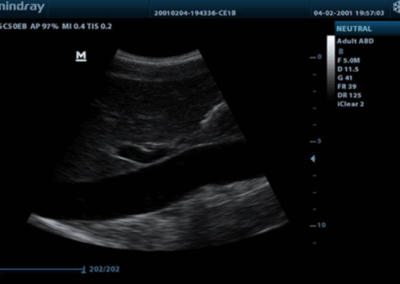

Z50

Sistema de diagnóstico ecográfico.

Con la combinación definitiva de alto rendimiento, aplicaciones clínicas integrales y diseño integrado, el Z50 lo ayudará a responder de manera más rápida y eficaz. El cambio de un sistema en blanco y negro a un sistema Doppler a color altamente eficiente ahora se ha vuelto más fácil y simple que nunca, lo que hace posible ir más allá de los límites y trascender lo habitual cuando se trata de la atención de los pacientes.